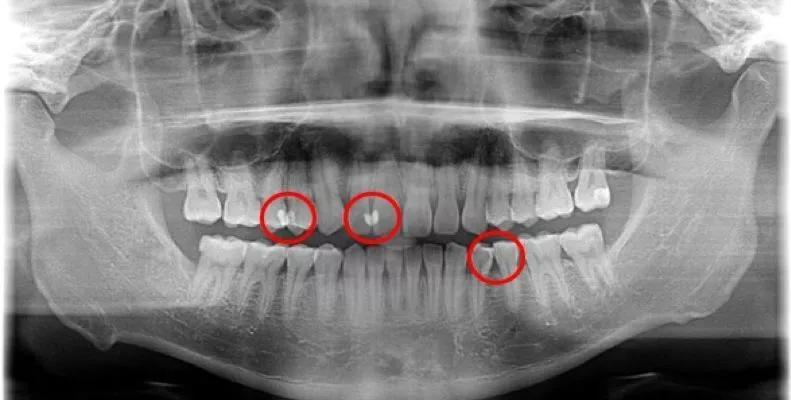

所以需要牙科ct(牙片)才能够观察到牙齿各项不易观察到的异常状态,包括邻面龋。

▶ 红色区域均为邻面龋